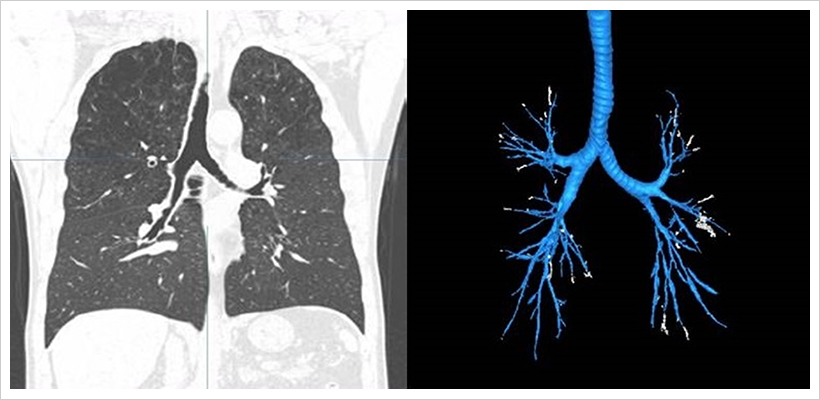

흉부 CT 사진(좌)과 기관지 인공지능 분석 결과(우)